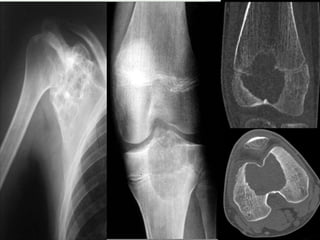

• X-rays

• epiphyseal

• well defined lytic lesions; either smooth or lobulated

margins with a thin sclerotic rim

• Internal calcifications can be seen in up to 40-60% of cases

• They range in size from 1-10cm, with most being 3-4cm at

diagnosis

• CT

• better delineation of the relationship to the growth plate

and articular surface

• Solid periosteal reaction (seen in up to 50% of cases) and

internal calcification (calcified matrix seen in ~ 1/2 of cases)

and cortical breach are also more easily appreciated.

• Endosteal scalloping may be

UMs

Y een